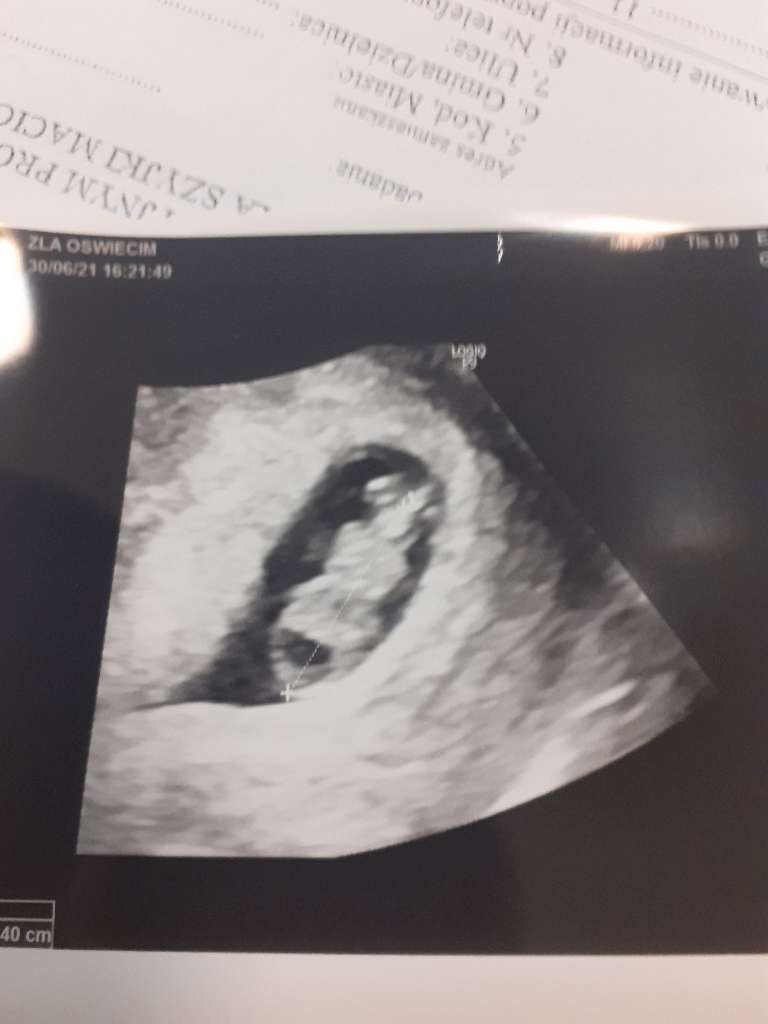

moje bejbi to już mały człowieczek

ma 2,5 cm

machał do mamuni rączka i nóżkami

Serduszko mocno bije

prawie 180 - lekarka mówi ze wszystko w jak najlepszym porządku